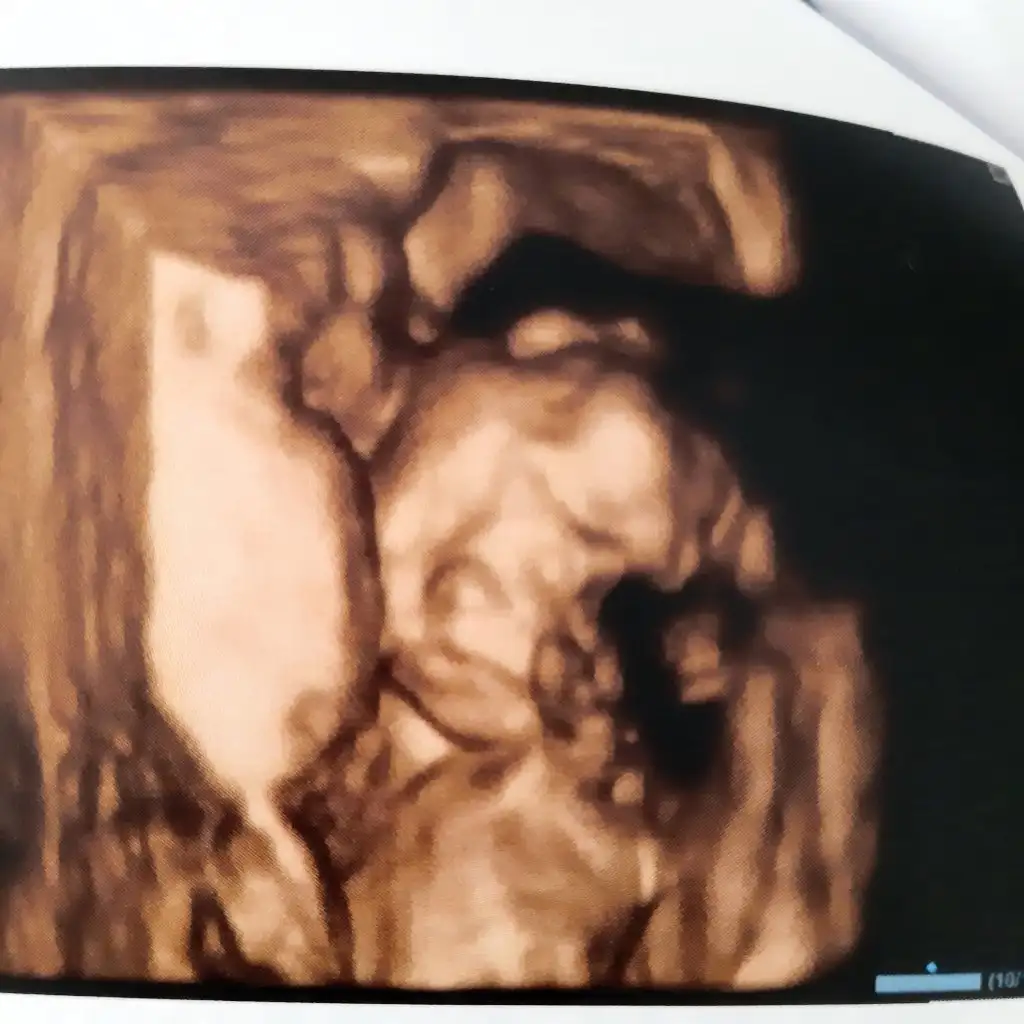

Hep ağzı açıktı. Bişiler aranıyorduOyy meme ariyo sanki ya agzini seveyim seninbenimkide tam tersi o kadar sert ve ciddi poz verdiki sanirsin bin pişman orda olduğuna

Oyy meme ariyo sanki ya agzini seveyim seninUyuyordu .tofıta atmıştım ağzına ama.geç yattım gece